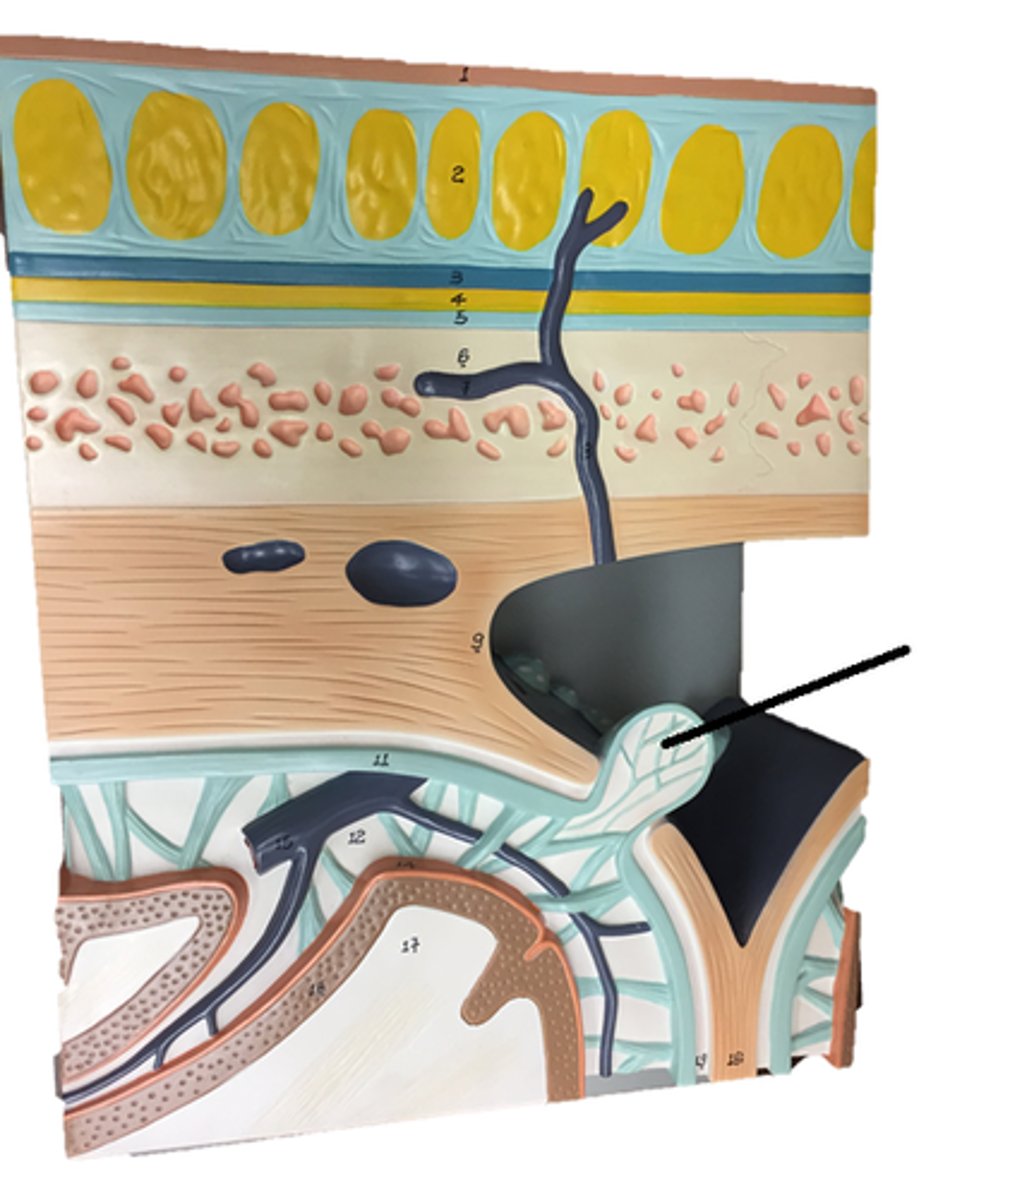

arachnoid villi

arachnoid mater of brain

dura mater of brain

pia mater of brain

subarachnoid space of brain